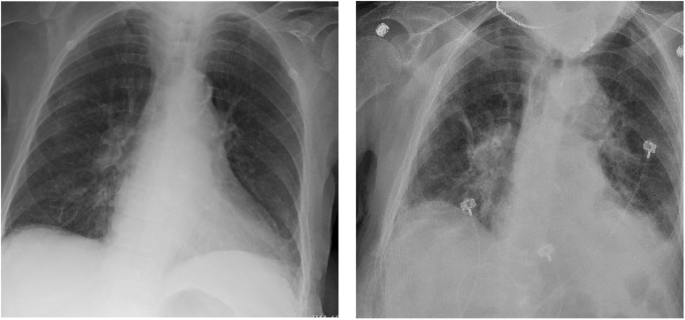

Upon arrival the emergency department, the patient was febrile to 100.7 F but was otherwise hemodynamically stable. On neurological examination, she was noted to be alert and oriented but intermittently confused. She demonstrated bilateral tremor-like movements of the upper and lower extremities without any evidence of convulsions, repetitive movements or rigidity. She had no sensory or motor deficits and her cranial nerve functions were intact. The complete blood count was notable for a pancytopenia with a white blood cell count of 1.8 103/μL, hemoglobin of 10.8 g/dL, hematocrit of 37.4% and platelets of 130 103/μL. Absolute neutrophil count was 0.9 103/μL and absolute lymphocyte count was 0.6 103/μL. The basic metabolic panel was notable for normal serum electrolytes and stable renal function. Alkaline phosphatase was slightly elevated to 139 U/L but hepatic function was otherwise unremarkable. Thyroid-stimulating hormone was elevated to 8.1 mIU/L, but thyroxine (T4) was within normal limits. Tacrolimus level was 3.1 mcg/L (lower than therapeutic range). Procalcitonin was 0.5 μg/L and her respiratory viral panel was negative. Two sets of blood cultures did not grow any organisms. Electrocardiogram showed normal sinus rhythm. Chest X-ray (Fig. 1, left) did not reveal any focal consolidation, pulmonary edema, pleural effusion or pneumothorax.

She subsequently underwent lumbar puncture, which revealed CSF that was clear in appearance with no xanthrochromia. The CSF analysis revealed 350 red cells/uL, 1 white blood cell/uL, 75% lymphocytes, 25% monocytes, glucose 67 mg/dL and protein 43 mg/dL. The CSF herpes simplex virus and varicella zoster virus polymerase chain reactions (PCR) were negative. The plasma cytomegalovirus and adenovirus testing were negative by PCR, and serologies indicated prior Epstein-Barr virus and Parvovirus B19 infection. On hospital day 3, the patient had persistent fevers and developed cough with dyspnea requiring oxygen supplementation. A chest X-ray revealed bilateral pulmonary infiltrate (Fig. 1, right). She therefore underwent SARS-CoV-2 PCR testing using a nasopharynx swab and was found to be positive. Sequencing of this SARS-CoV-2 isolate revealed a virus similar to other SARS-CoV-2 circulating in the region (https://nextstrain.org/ncov?s=USA/CT-Yale-009/2020).